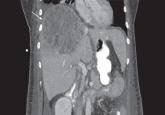

Pyogenic liver abscess